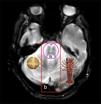

Atrofia multisistémica: signo de la cruz y de Santiaguiño

Multiple system atrophy: Hot cross bun and Santiaguiño sign